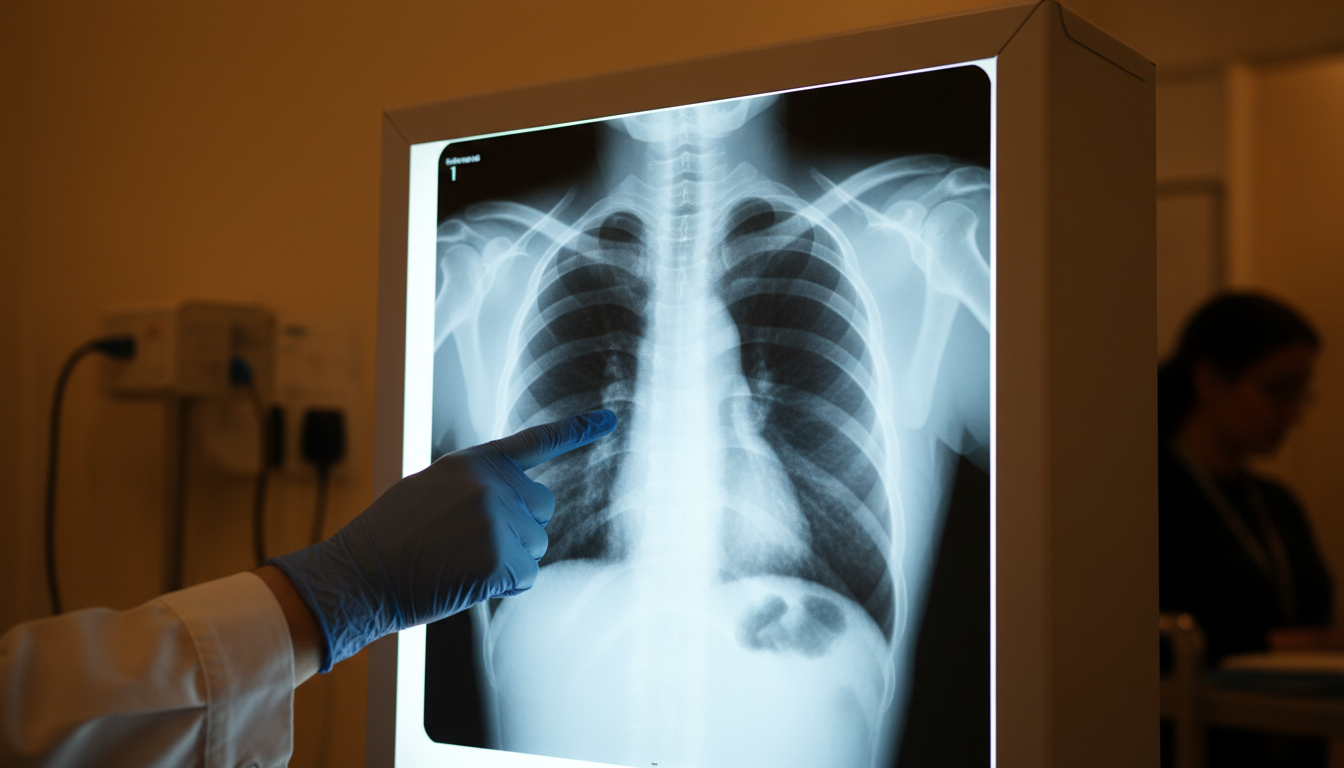

Quand le mucus brun laisse place à du sang en mars 2025, les médecins ne peuvent plus détourner le regard. Une radio pulmonaire révèle une ombre suspecte sur son poumon droit. Mais même là, on la rassure : « Avec votre âge, on est sûrs à 99 % que ce n’est pas un cancer. Ne vous inquiétez pas. » Ce genre d’erreur de diagnostic peut coûter des années de vie. Pour Kayley, c’est exactement ce qui s’est passé.